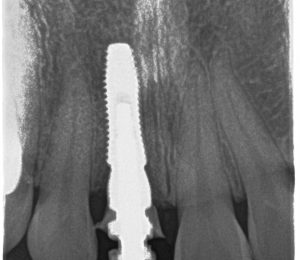

Răng cửa giữa bị mất lâu ngày – dẫn đến tụt nướu, tiêu xương (Bệnh nhân đang mang răng tạm)

Răng cửa giữa bị mất lâu ngày – xương vùng răng mất bị tiêu lõm so với răng bên cạnh

- Cấy ghép implant

- Ghép xương + Mô mềm tạo hình nướu